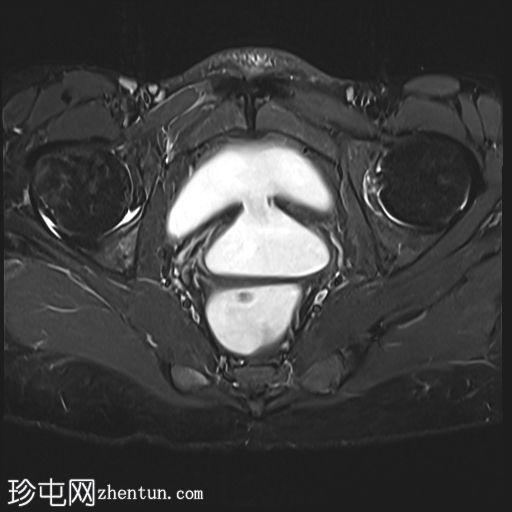

膀胱充盈后

MRI

矢状位

T2加权像

膀胱后壁与阴道前壁之间存在宽阔的瘘管。膀胱内可见气液平面。

阴道后穹窿上部与直肠中段前壁之间可见另一条较小的瘘管。在重扫描T2加权像上也可见。

子宫未见局灶性病变。

左侧卵巢可见液性囊肿。

盆腔少量游离液体。